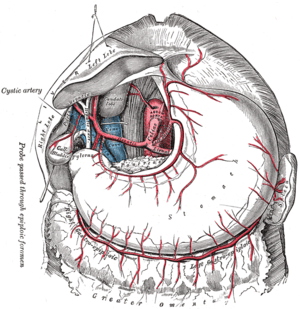

Blood supply

Near the middle of the spleen lies a long fissure, the splenic hilum. The hilum is the point of attachment for the gastrosplenic ligament, and the point of insertion for the splenic artery and splenic vein. There are other openings present for lymphatic vessels and nerves.

Like the thymus, the spleen possesses only efferent lymphatic vessels. The spleen is part of the lymphatic system. Both the short gastric arteries and the splenic artery supply it with blood.[11]

The celiac artery and its branch.

The celiac artery and its branch. Horizontal disposition of the peritoneum in the upper part of the abdomen.